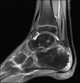

Calcaneal spur

A calcaneal spur (also known as a heel spur) is a bony outgrowth from the calcaneal tuberosity (heel bone). Calcaneal spurs are typically detected by x-ray examination. [Source: Wikipedia ]